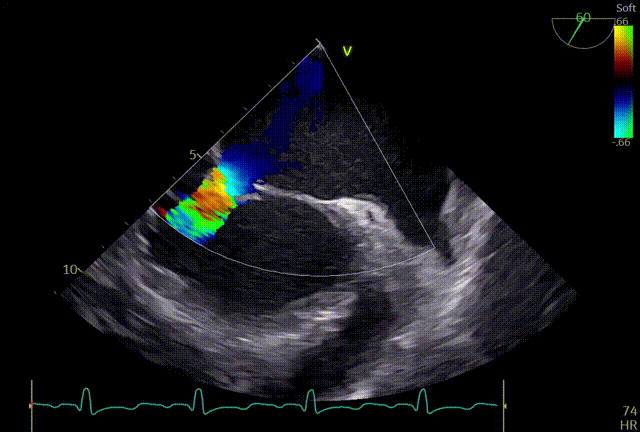

反流情况

术前TEE及左房压

1区

1区带彩

2区

2区带彩

3区

3区带彩

3D

3D带彩